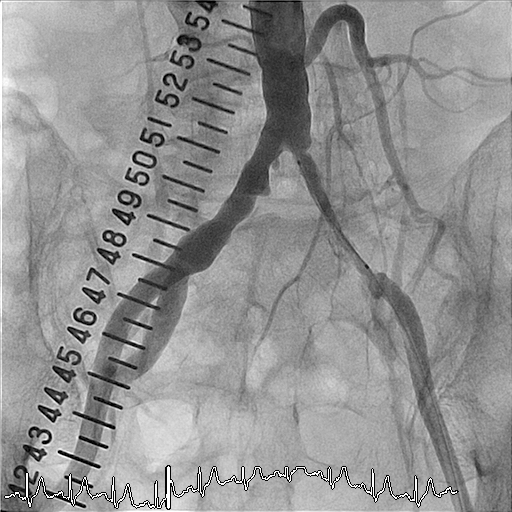

治療前

左総腸骨動脈が閉塞している事が造影で確認出来ます。